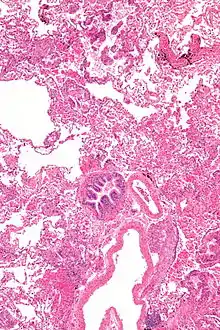

Pathology

Grossly, LAM lungs are enlarged and diffusely cystic, with dilated air spaces as large as several centimeters in diameter.[105][106] Microscopic examination of the lung reveals foci of smooth muscle-like cell infiltration of the lung parenchyma, airways, lymphatics, and blood vessels associated with areas of thin-walled cystic change. LAM lesions often contain an abundance of lymphatic channels, forming an anastomosing meshwork of slit-like spaces lined by endothelial cells. LAM cells generally expand interstitial spaces without violating tissue planes but have been observed to invade the airways, the pulmonary artery, the diaphragm, aorta, and retroperitoneal fat, to destroy bronchial cartilage and arteriolar walls, and to occlude the lumen of pulmonary arterioles.[105]

There are two major cell morphologies in the LAM lesion: small spindle-shaped cells and cuboidal epithelioid cells.[107] LAM cells stain positively for smooth muscle actin, vimentin, desmin, and, often, estrogen and progesterone receptors. The cuboidal cells within LAM lesions also react with a monoclonal antibody called HMB-45, developed against the premelanosomal protein gp100, an enzyme in the melanogenesis pathway.[107] This immunohistochemical marker is very useful diagnostically, because other smooth muscle–predominant lesions in the lung do not react with the antibody.[108] The spindle-shaped cells of the LAM lesion are more frequently proliferating cell nuclear antigen positive than the cuboidal cells, consistent with a proliferative phenotype.[107] Compared with cigar-shaped normal smooth muscle cells, spindle-shaped LAM cells contain less abundant cytoplasm and are less eosinophilic. Estrogen and progesterone receptors are also present in LAM lesions,[109][110][111] but not in adjacent normal lung tissue.[112] LAM lesions express lymphatic markers LYVE-1, PROX1, podoplanin and VEGFR-3. The smooth muscle–like cells of AMLs are morphologically and immunohistochemically similar to LAM cells, including reactivity with antibodies directed against actin, desmin, vimentin, and HMB-45 as well as estrogen and progesterone receptors.[113][114] Unlike the dilated airspaces in emphysema, the cystic spaces found in LAM may be partially lined with hyperplastic type II cells.[115]